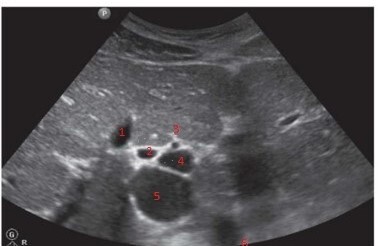

19

Q

Label the structures

A

1. GB

2. BD

3. HA

4. MPV

5. IVC

6. AO